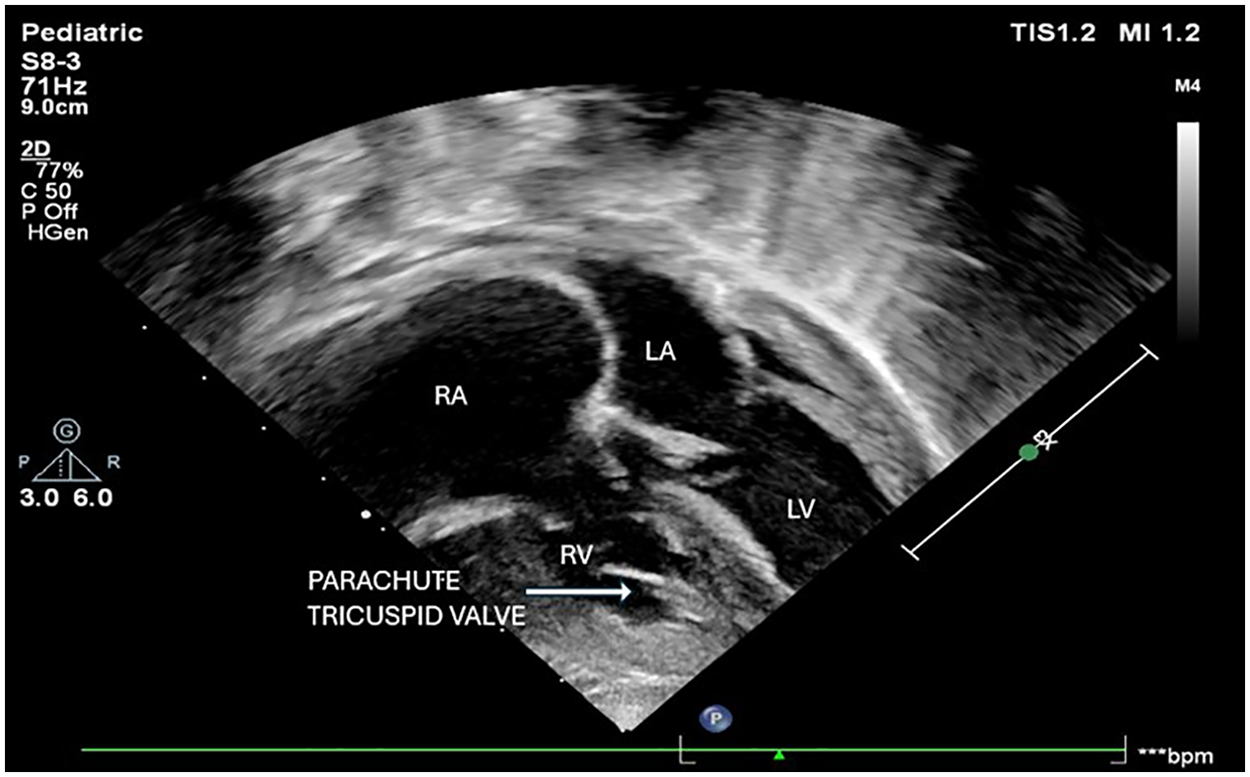

Parachute Tricuspid Valve in Association with Cyanotic Congenital Heart Disease and Juxtaposed Atrial Appendages in a 1-Year-Old Male: A Rare Anatomical Association

Abstract Parachute tricuspid valve (PTV) is an exceedingly rare congenital anomaly, often found in association with acyanotic heart defects. Its occurrence in association with cyanotic congenital heart disease (CCHD) is even less common. We report the case of a 1-year-old male presenting with complex cyanotic heart disease along with parachute tricuspid valve. Detailed evaluation revealed a constellation of anomalies, including parachute tricuspid valve in association with double outlet right ventricle (DORV) with D-malposed great arteries, severe pulmonary stenosis, and a non-routable ventricular septal defect. Echocardiography played a vital role in defining the complex anatomy and guided the decision toward single-ventricle palliation. This case underscores the importance of meticulous anatomical assessment in patients with congenital heart disease and adds to the sparse literature on this rare condition.

Cyanotic congenital heart disease, Double Outlet Right Ventricle, Parachute tricuspid valve, Pulmonary stenosis, Ventricular septal defect